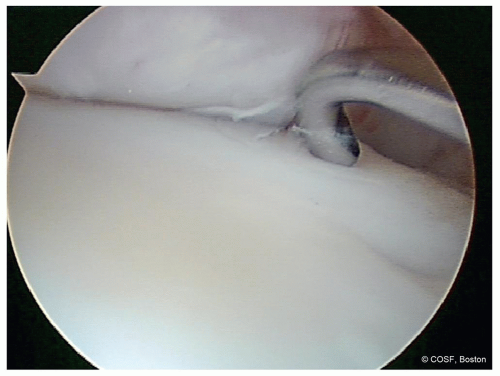

Palpate with probe to assess for softness and stability (Figure 34.3)

Probe to test overlying cartilage

Often will be unstable in talus OCD

Use arthroscopic probe to assess the size, location, and stability of the lesion (Figure 34.9)

Grade/stage the lesion based on surgical appearance combined with imaging classification

Cheng (1995) Arthroscopic Staging

Stage A Smooth, intact, ballotable

Stage B Rough surface, stable

Stage C Fibrillation, fissuring, stable (see Figure 34.3)

Stage D Flap present, unstable

Stage E Loose nondisplaced fragment, unstable

Stage F Displaced fragment, unstable (Figure 34.11)